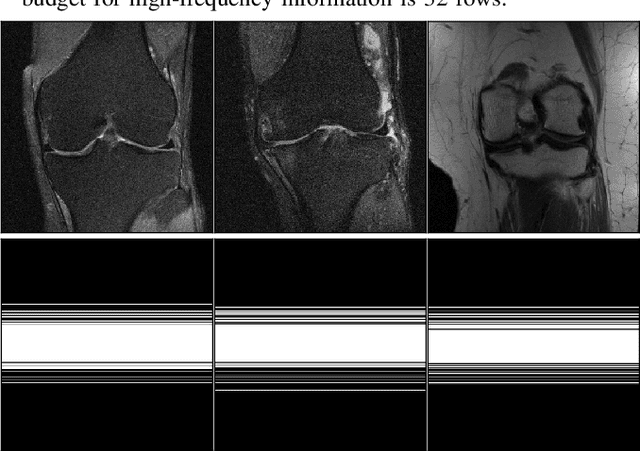

There is much recent interest in techniques to accelerate the data acquisition process in MRI by acquiring limited measurements. Often sophisticated reconstruction algorithms are deployed to maintain high image quality in such settings. In this work, we propose a data-driven sampler using a convolutional neural network, MNet, to provide object-specific sampling patterns adaptive to each scanned object. The network observes very limited low-frequency k-space data for each object and rapidly predicts the desired undersampling pattern in one go that achieves high image reconstruction quality. We propose an accompanying alternating-type training framework with a mask-backward procedure that efficiently generates training labels for the sampler network and jointly trains an image reconstruction network. Experimental results on the fastMRI knee dataset demonstrate the ability of the proposed learned undersampling network to generate object-specific masks at fourfold and eightfold acceleration that achieve superior image reconstruction performance than several existing schemes. The source code for the proposed joint sampling and reconstruction learning framework is available at https://github.com/zhishenhuang/mri.